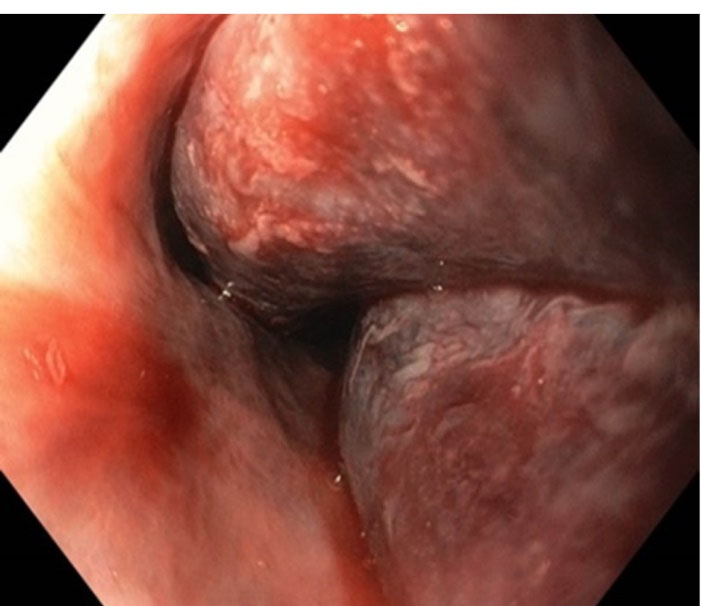

The heparin was stopped. Aspirin was continued throughout but clopidogrel was stopped and added at the time of discharge After initial resuscitation, a UGIE was done, which showed a bluish discoloration in the wall of the esophagus, from middle to the lower part (). There was no active bleed present.A Computed Tomography (CT) Angiography was done which was consistent with the diagnosis of EIH (). The clinical diagnosis of EIH is important in ruling out other differentials, which may have worse prognosis.

Figure 1.

UGIE done showing a bluish discoloration in the posterior wall of the oesophagus suggestive of intramural haematoma

The diagnosis of EIH is established by endoscopy and radiology. In Upper GI Endoscopy, the haematoma is seen as a bluish discoloration located most commonly in the lower part of the esophagus as it is deficient in striated muscles and other supporting structures.2 Radiological investigations include CECT, Magnetic Resonance Imaging (MRI), and CT/MRI Angiography. The typical appearance on CT is of an eccentric hyperattenuating mass in the wall of the esophagus.8 MRI may be used to better delineate the soft tissue planes.